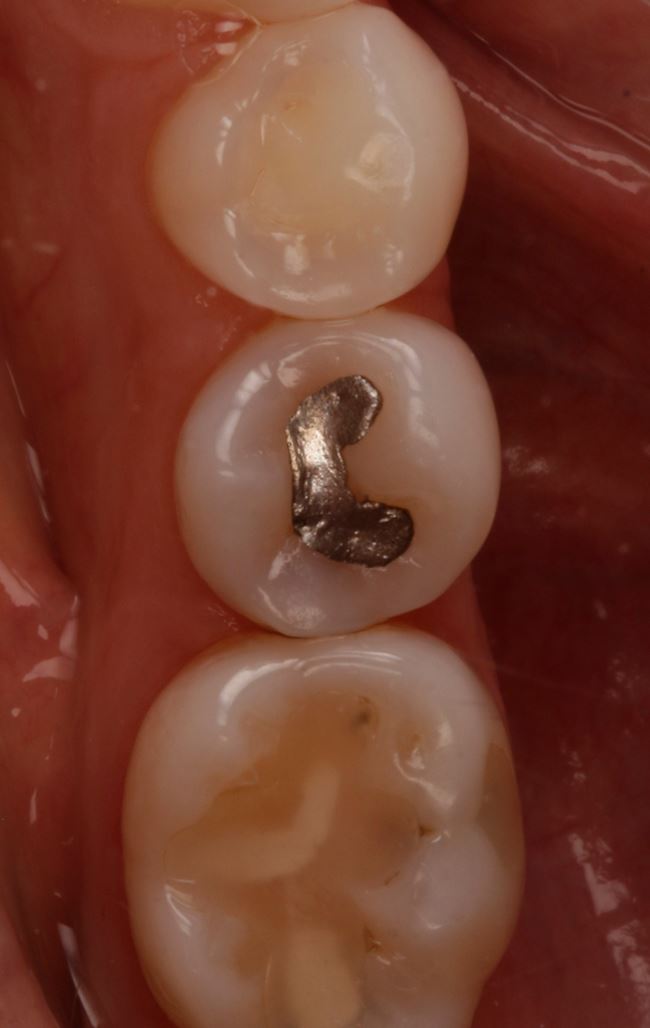

W przypadku zęba 45 wyraźnie widać, że DIAGNOcam się sprawdził, gorzej ze zdjęciem skrzydłowo-zgryzowym. Teraz pozostało już tylko założenie formówki (ryc. 11), wypełnienie ubytku, w tym przypadku nanohybrydowym materiałem kompozytowym Harmonize (Kerr) (ryc. 12 i 13), dostosowanie wypełnienia i wypolerowanie (ryc. 14). Chociaż to jeszcze nie wszystko. Ostatnią czynnością powinno być zmotywowanie pacjentki do codziennego stosowania nici dentystycznej. Obrazy z DIAGNOcamu świetnie się do tego nadają.

Ryc. 14. Ubytek w zębie 45 bezpośrednio po wypełnieniu materiałem Harmonize Enamel A3.

Ryc. 15. Ząb 45 po leczeniu.